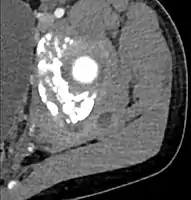

CT with IV contrast showing enlargement and heterogeneous hypodensity in the right pectoralis major muscle. A focal abscess collection with gas within it is present medially. There are enlarged axillary lymph nodes and some extension into the right hemithorax. Note the soft tissue and phlegmon surrounding the right internal mammary artery and vein. The patient was HIV+ and the pyomyositis is believed to be due to direct inoculation of the muscle related to parenteral drug abuse. The patient admitted to being a "pocket shooter" CT with IV contrast showing enlargement and heterogeneous hypodensity in the right pectoralis major muscle. A focal abscess collection with gas within it is present medially. There are enlarged axillary lymph nodes and some extension into the right hemithorax. Note the soft tissue and phlegmon surrounding the right internal mammary artery and vein. The patient was HIV+ and the pyomyositis is believed to be due to direct inoculation of the muscle related to parenteral drug abuse. The patient admitted to being a "pocket shooter"